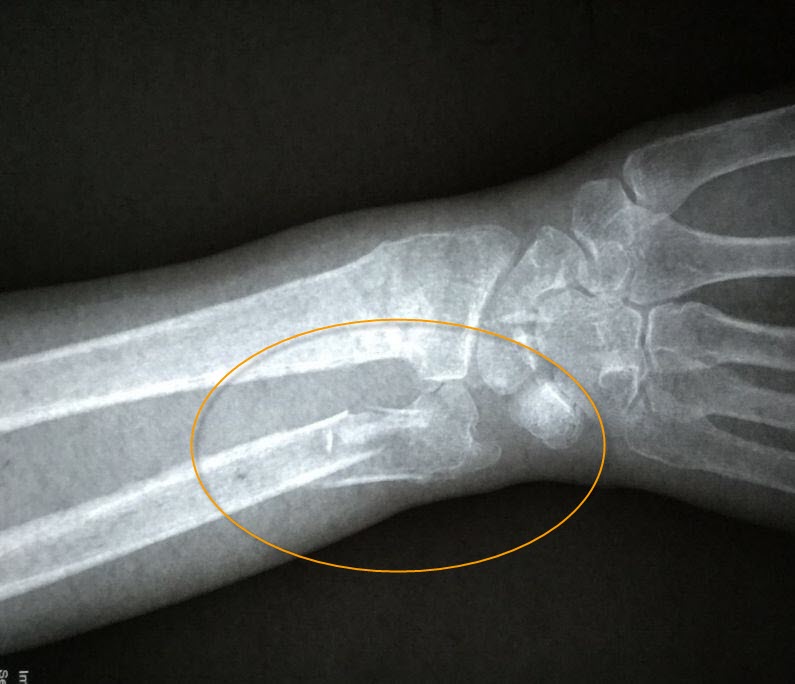

【明慧网二零一九年二月二十四日】〖大陆来稿〗二零一九年一月二十八日上午十时许,现年八十三周岁的北京市民善珍奶奶(化名)在家中客厅穿衣时,不慎摔倒,右手腕部戳在餐桌一角,很疼痛。当时家人将老人送至就近医院检查,拍片结果显示如图1。检查报告单中描述为:右侧桡骨、尺骨远段可见骨质断裂,骨折端掌侧成角,远折端背侧移位(图2)。

'图2'

图2